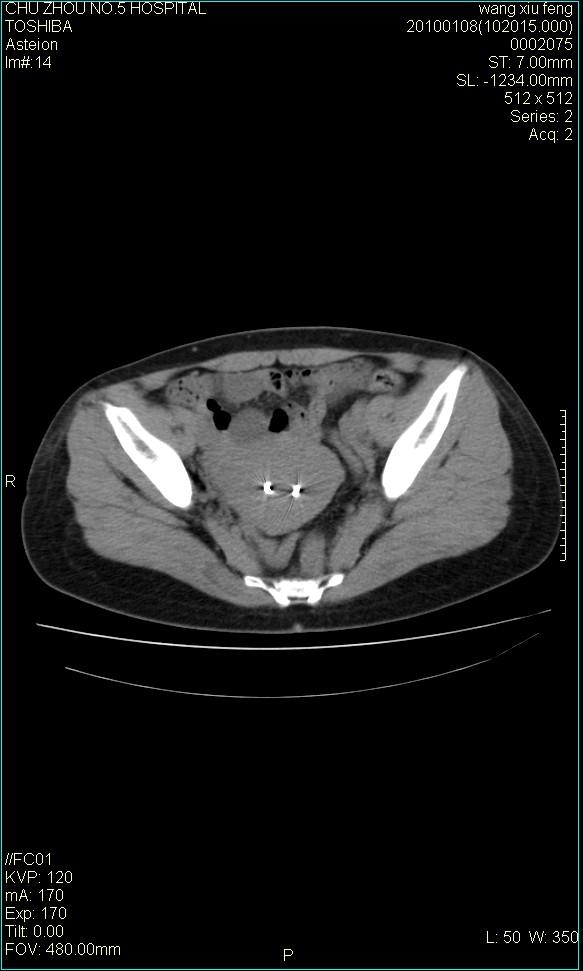

标题: CT24042:子宫右上方囊性包块,性质???? [打印本页]

标题: CT24042:子宫右上方囊性包块,性质????

f-41,左乳腺ca术后4年,b超示:子宫右上方囊性包块约5.5*3.4cm,前日行胸部ct平扫未见明显异常。

囊腺瘤,转移瘤不排除。

考虑右侧卵巢囊腺瘤?

右侧卵巢囊肿或小囊腺瘤。

考虑右侧卵巢囊腺瘤?建议增强!

考虑右侧卵巢囊腺瘤。

考虑右侧卵巢囊性占位性病变(囊肿?囊腺瘤?)。